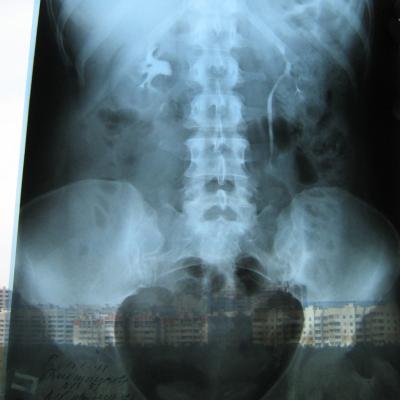

Была сделана операция 04.07.2012г по поводу нефропексии правой почки поясничной мышцей с помощью разреза. После операции болит правая сторона живота и в спине и в пояснице был затронут нерв, и до сих пор правая нога до колен не отходит спереди и сбоку. Через полтора месяца после операции образовался отек, пошло воспаление сзади на спине, потому что был затронут нерв. Сделала урографию через 4 месяца после операции. Если вас не затруднит, посмотрите пожалуйста снимки, правильно ли располагается мочеточник правый после операции. Скажите пожалуйста, посмотрев мои снимки, правильное ли расположение мочеточника и почему болит правая сторона живота все это время, и каким исследованием теперь после операции проверить что там творится в животе, что там затронуто? Все указывает на то что был затронут нерв, оперирующий врач говорит что не может быть такого, а я уже почти всю ногу правую не чувствую

Снимки прикрепляю

Абсолютно нормальное расположение почки и мочеточника . Но ведь и онемение нижней конечности с положением почки не связано. Есть такое понятие "футлярный синдром"- после вынужденного положения конечности. Проконсультируйтесь с неврологом.